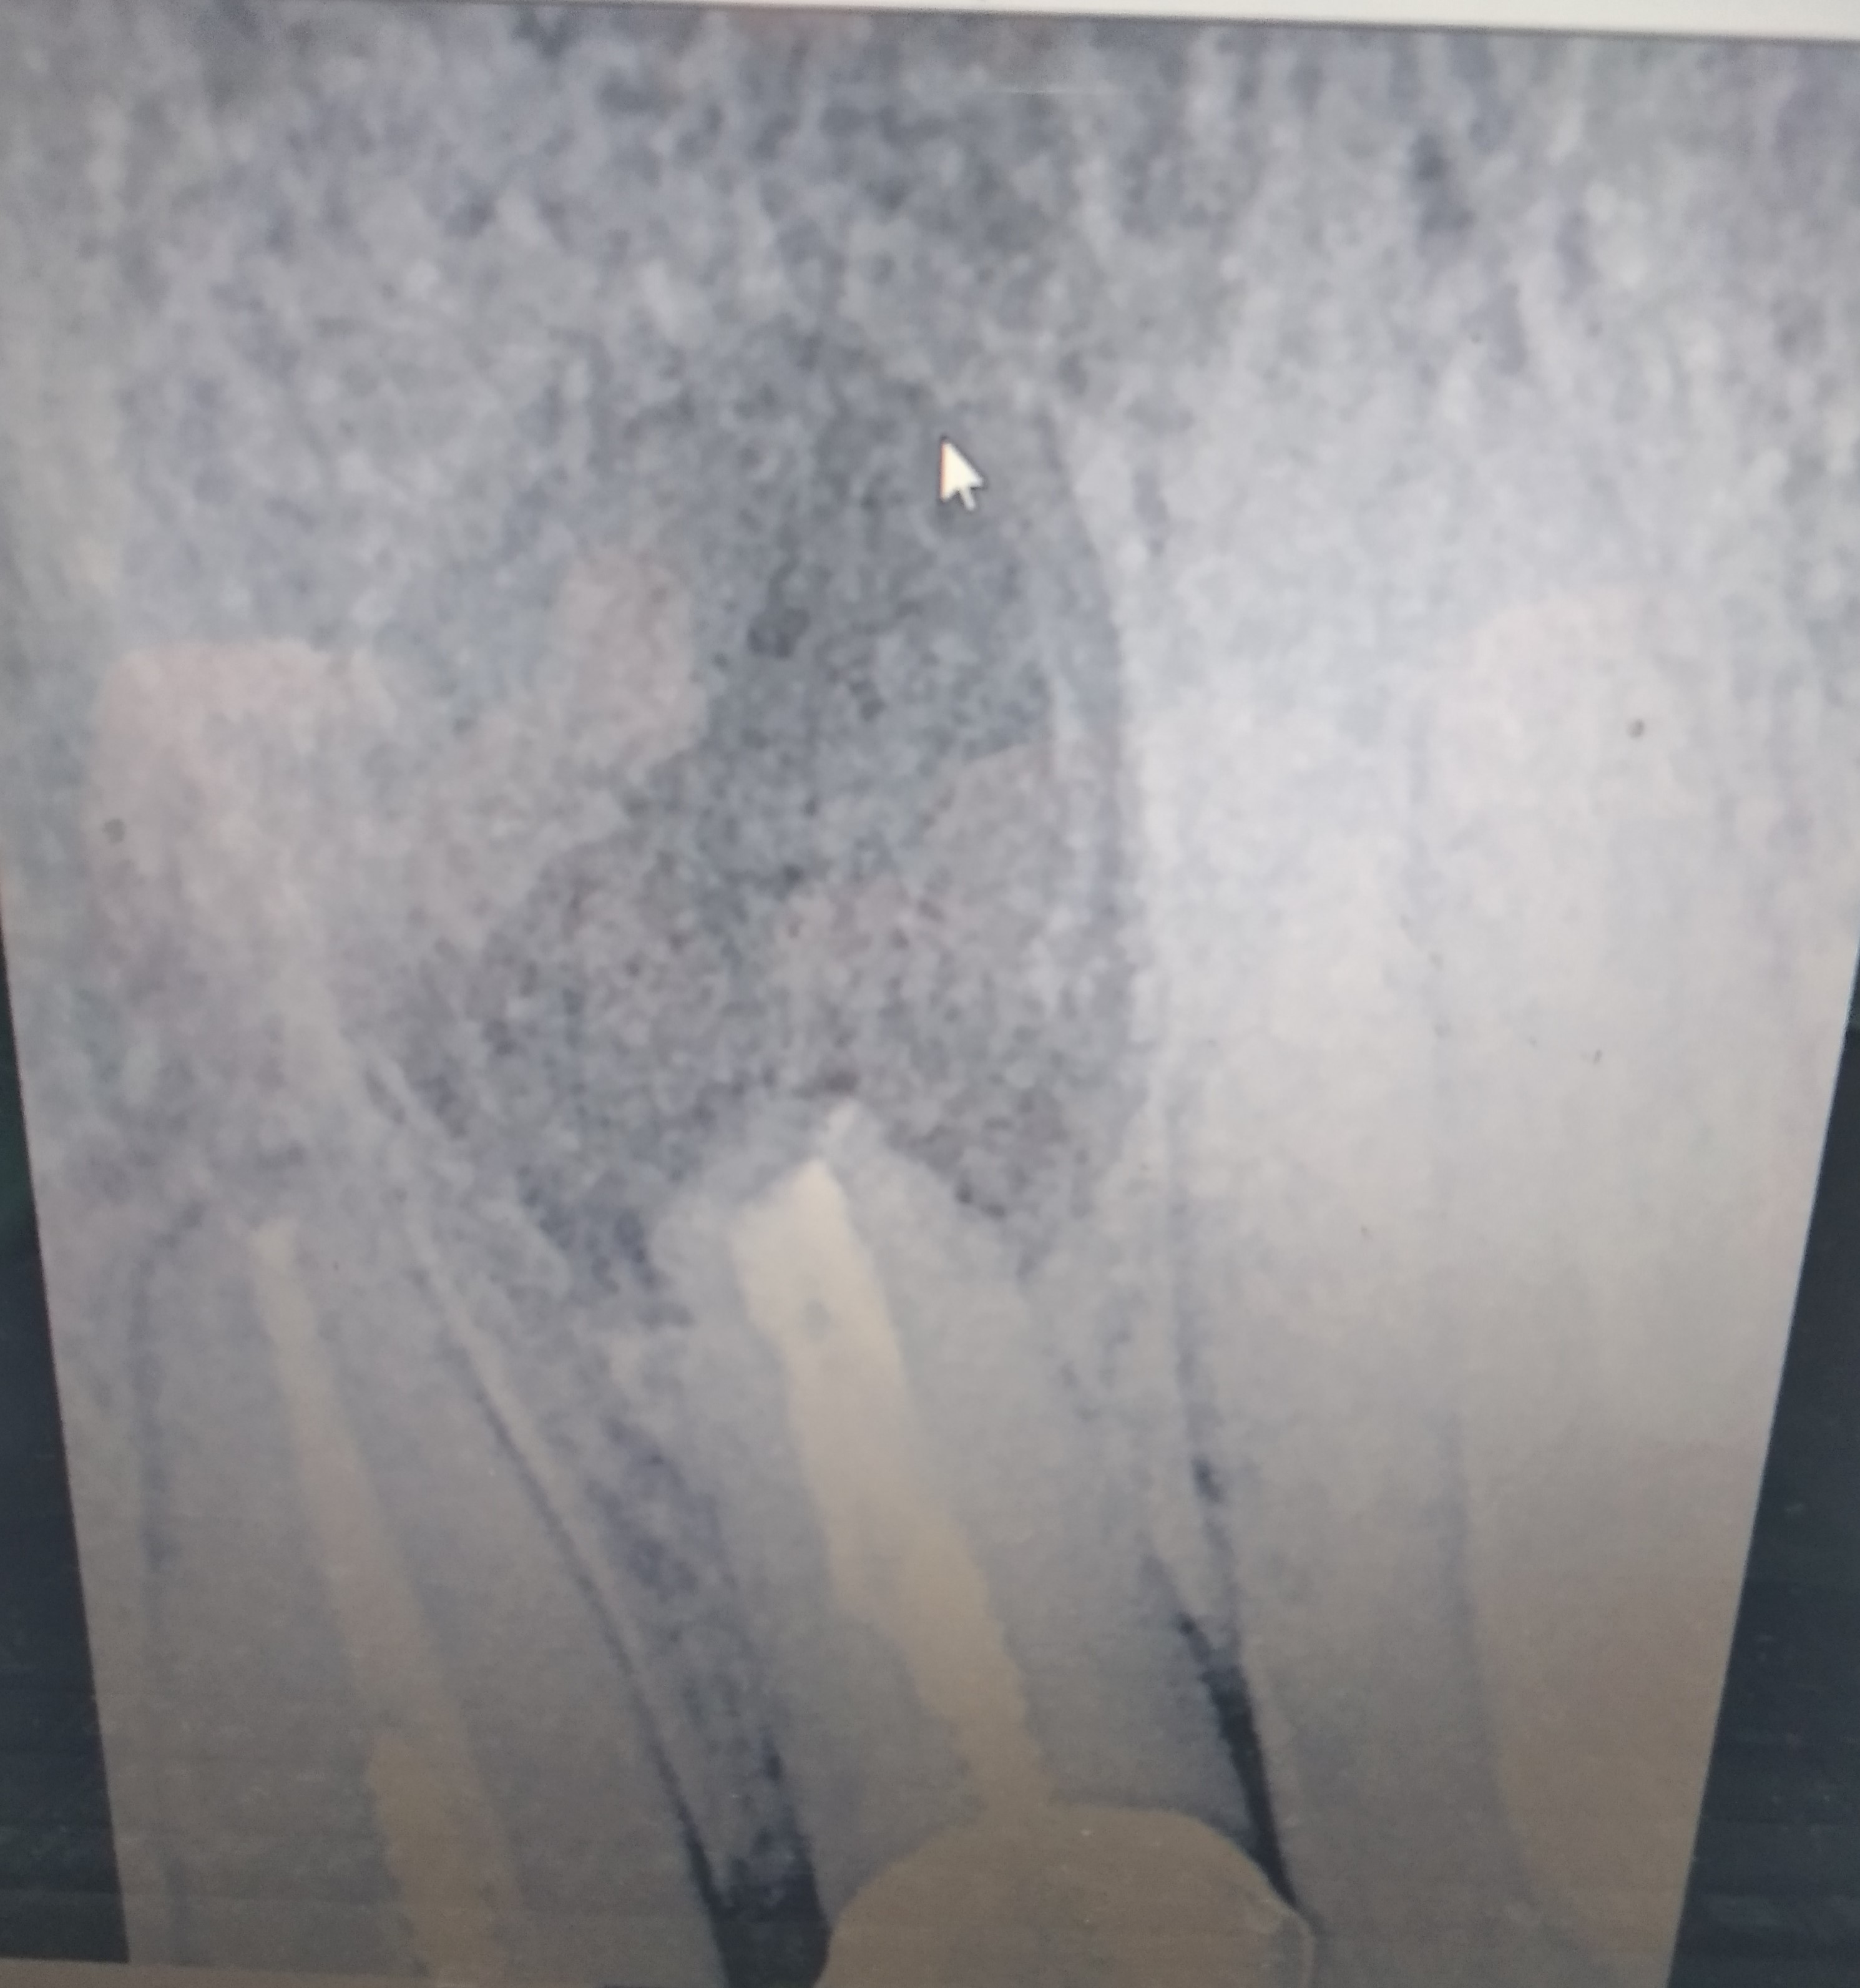

Ситуація наступна: 10 років тому на передньому верхньому зубі робилася резекція верхівки кореня і чистка, була кіста. після того 5 років тому на передні 4 зуби встановлені коронки парні(1 і 2 зуби разом). Перед установкою неоднократно робилися рентгени, стоматолог дуже позитивно відзивався і говорив що проблем жодних не може бути.

Днями помітив що болить при натисканні на ясна біля носа, саме там де колись робилася резекція/чистка. Візит до мого стоматолога чесно не надто порадував - він зробив рентген і сказав що ситуація не критична, але він пропонує 2 варіанти - як основний і альтернативу:

ще один знімок